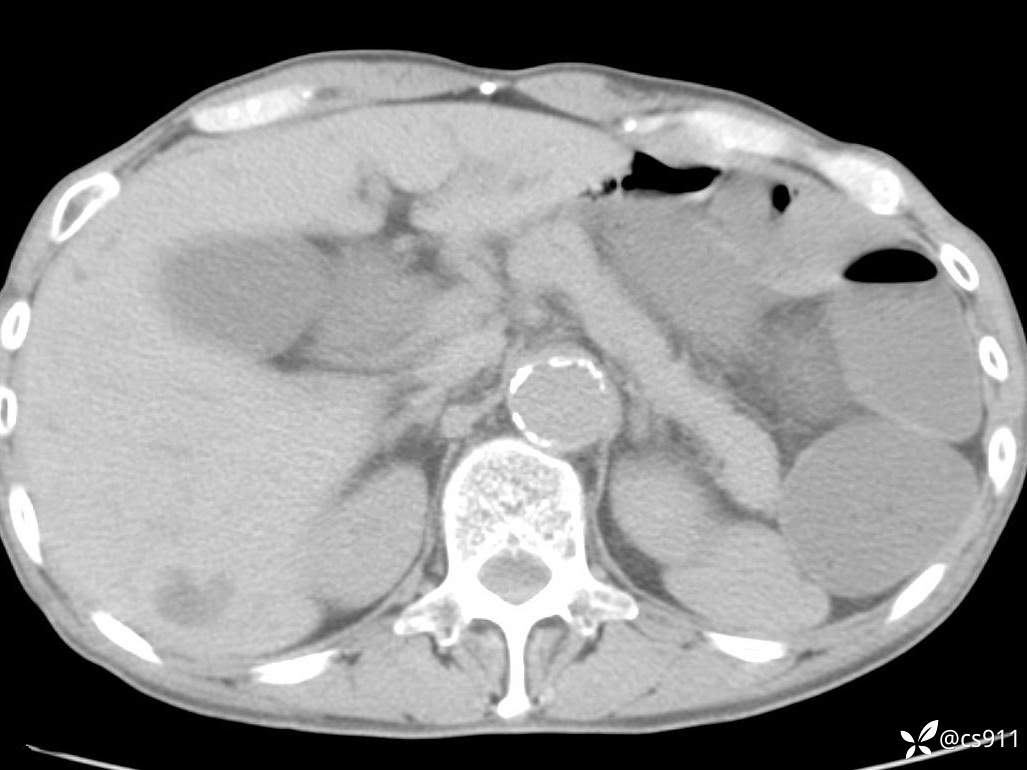

急腹症之急诊CT,原因?答案公布

男,77岁,腹痛、腹胀伴恶心呕吐1天。呕吐胃内容物,非喷射性呕吐,有咖啡色样胃内容物,诉有胃穿孔病史。查体:全腹平,下腹部压痛,全腹无反跳痛,叩诊呈浊音,移动性浊音阴性,肠鸣音减弱,1-2次/分。肛检:直肠未扪及明显肿物,可触及大量粪块。

T 36.6℃ P 80次/分 R 26次/分 BP 100/60mmHg

白细胞(WBC) H 14.55 10e9/L 4-10

中性粒细胞百分率(NEUT%) H 85.7 % 40-75

血淀粉酶(AMY) HH 1859 U/L 35-135

癌胚抗原(CEA) H 27.44 ng/ml 0-5

呕吐物 潜血试验 * 阳性 阴性

患者轮椅入室检查神志清楚, 能配合摆位和呼吸